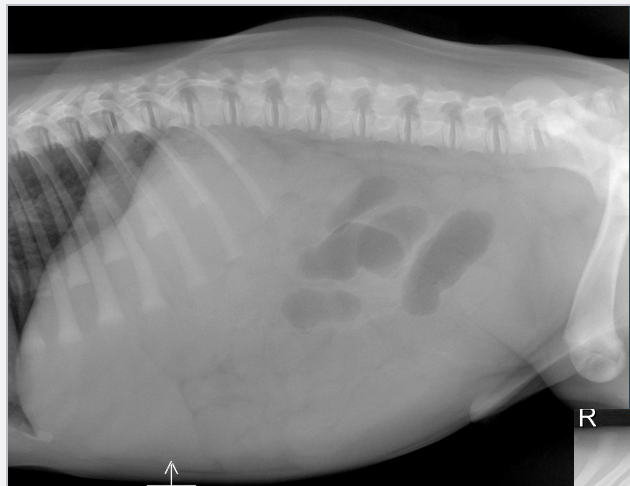

What is shown in these images?

A

normal abdomen and normal body wall in a dog